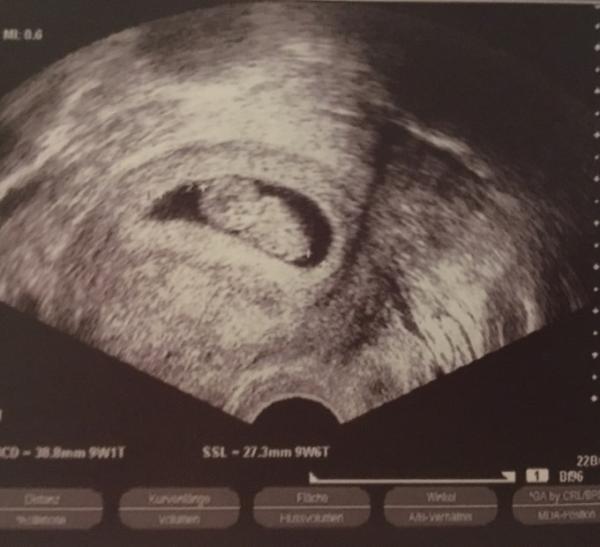

Hallo Mädels. Gestern hatten doch einige von uns einen Termin beim Arzt oder? Hab bisher nur von einem gesehen? Ich war auch beim Arzt. Alles super. Unterschied sich nur um 2,3 Tage. Das wäre noch kein Grund den et zu korrigieren. Alles so wie es zu dieser Zeit sein soll. Zwei Ärmchen, zwei Beinchen, Herzschlag... Bin heute 8+5, also gestern 8+4 und das Möhnchen war 8+2. Alles tutti

Bild zu Gestern beim Frauenarzt - Forum für April - Mamis